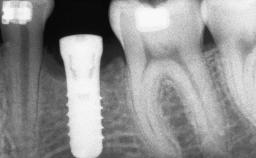

Ridge Preservation and Implant Placement for a Fixed Dental Prosthesis After a Car Accident

It is well known to clinicians that any removal of teeth will, over time, cause the dimensions of the alveolar ridge to be reduced by resorption of the bundle bone and by changes related to external modeling. This development is particularly evident in the crestal region with its thin buccal bone that consists of bundle bone almost entirely. The facial bone will rapidly resorb as blood supply from the periodontal ligament gets disrupted (Araújo and Lindhe 2005). There is no reason why traumatic tooth loss should not have the same consequences. It takes more than achieving implant osseointegration for a treatment outcome to be considered successful. No deficiency of bone or soft tissue is acceptable when an ideal esthetic outcome is the goal. Several articles (Sanz and coworkers 2011; Vignoletti and coworkers 2011) have reported on techniques of improving the alveolar ridge for implant treatment, notably focusing on protecting tissues from resorption.

# of Implants 4

Bone Augmentation Horizontal|Simultaneous|Sinus Floor Elevation|Staged